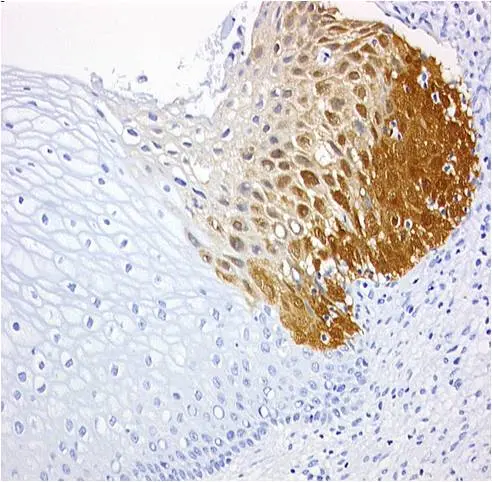

Gewebeschnitt vom Gebärmutterhals: Die braune Färbung ist ein Indiz für bösartig veränderte Zellen.

Das Unternehmen entwickelte den Test und brachte ihn unter dem Namen CINtec PLUS auf den Markt. Das immunhistologische Verfahren weist das gleichzeitige Vorhandensein der beiden Biomarker p16 und Ki-67 in einer einzigen Zelle nach. Ein positives Ergebnis signalisiert, dass eine HPV-infizierte Frau schon eine Krebsvorstufe entwickelt hat, die der sofortigen klinischen Abklärung bedarf. HPV-positive Frauen dagegen, bei denen der Test negativ ausfällt, haben keine Krebsvorstufe entwickelt, daher können die weiteren Vorsorgeintervalle wesentlich verlängert werden.